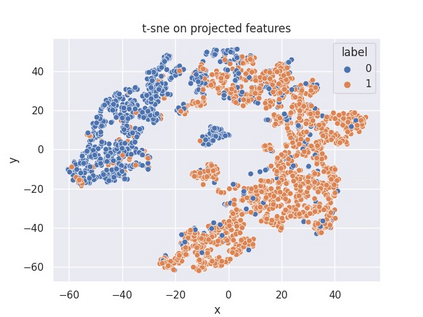

Multiple instance learning (MIL) is a powerful approach to classify whole slide images (WSIs) for diagnostic pathology. A fundamental challenge of MIL on WSI classification is to discover the \textit{critical instances} that trigger the bag label. However, previous methods are primarily designed under the independent and identical distribution hypothesis (\textit{i.i.d}), ignoring either the correlations between instances or heterogeneity of tumours. In this paper, we propose a novel multiplex-detection-based multiple instance learning (MDMIL) to tackle the issues above. Specifically, MDMIL is constructed by the internal query generation module (IQGM) and the multiplex detection module (MDM) and assisted by the memory-based contrastive loss during training. Firstly, IQGM gives the probability of instances and generates the internal query (IQ) for the subsequent MDM by aggregating highly reliable features after the distribution analysis. Secondly, the multiplex-detection cross-attention (MDCA) and multi-head self-attention (MHSA) in MDM cooperate to generate the final representations for the WSI. In this process, the IQ and trainable variational query (VQ) successfully build up the connections between instances and significantly improve the model's robustness toward heterogeneous tumours. At last, to further enforce constraints in the feature space and stabilize the training process, we adopt a memory-based contrastive loss, which is practicable for WSI classification even with a single sample as input in each iteration. We conduct experiments on three computational pathology datasets, e.g., CAMELYON16, TCGA-NSCLC, and TCGA-RCC datasets. The superior accuracy and AUC demonstrate the superiority of our proposed MDMIL over other state-of-the-art methods.